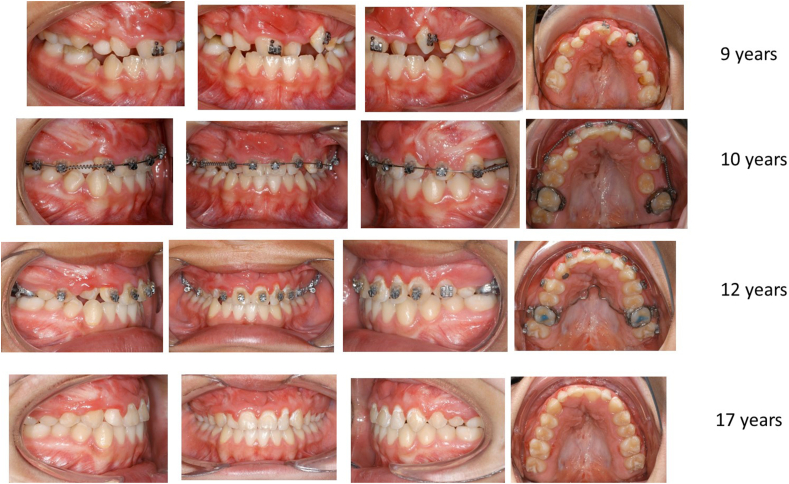

Fig. 9.

a+b:. Bilateral CLP. Facial and maxillary development after bilateral cleft lip and palate.

Bilateral CLP, same patient as in Fig. 8. Occlusion after bilateral cleft lip and palate, development over 17 years, orthodontic treatment, no corrective surgery.

It should also be noted that the development of the nose was clinically normal and that it was well shaped (Fig. 8) Orthodontic treatment, if required, was started before any alveolar bone grafting procedures, at the age of about 7 years, after eruption of the lateral incisors, as recommended by Semb et al.16

Between 1995 and 2016, 2358 primary cleft patients, including 68 bilateral CLAP patients, underwent surgery by the author according to the described concept, with follow-up performed by a multidisciplinary CLAP team on a regular basis. In these special consulting sessions, the children were examined by oral and maxillofacial surgeons, otolaryngologists/audiologists, orthodontists and speech therapists. The clinical examinations included hearing assessment, speech assessment consisting of conventional speech/language evaluation, NasalView system analysis and, if necessary, nasendoscopy, as well as model analysis and cephalometric analysis according to Delaire.13,14 Hearing and speech/language assessments confirmed normal development of the children corresponding to the results in unilateral CLAP patient.14,15 Good alignment of the premaxilla, which before surgery had been in an anterior position, and good dental arch form, were achieved under the influence of the normalised musculature up to 6 years of age, with only one patient, with an extremely protrusive premaxilla, undergoing preoperative orthodontic treatment. Our results also showed good transverse development of the maxillary arch and good occlusion (Fig. 8). Sagittal midfacial growth was normal, and there were nearly normal cephalometric values (Table 1) (see Fig. 9).